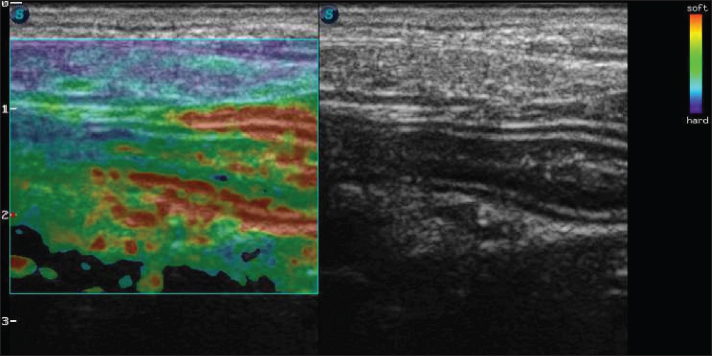

An abdominal ultrasound was performed using SAEVO® FT422 equipment with an 8.0-MHzz multi-frequency microconvex transducer. Gastric thickening (0.71 cm) was observed in the accessible portions, with preserved stratification and a mucosal layer containing intramural gas, suggesting gastritis and gastric pneumatosis. The duodenum and jejunum were also thickened (0.56 and 0.40 cm, respectively), maintaining their layered pattern. The intestinal mucosa exhibited thickening and hyperechogenicity, with coalesced hyperechoic echoes on the luminal surface (Fig. 1A), indicating inflammation associated with lymphangiectasia. Additionally, an enlarged jejunal lymph node was noted, characterized by regular margins, homogeneous echotexture, preserved echogenicity, and dimensions of 4.63 × 1.53 cm (Fig. 1B).

Fig. 1. B-mode ultrasound of a dog with intestinal lymphangiectasia. A: Duodenum with hyperechogenic mucosa at the dorsal and ventral margins. B-Jejunal lymph node with regular margins, homogeneous echotexture, and preserved echogenicity.

An abdominal ultrasound can show intestinal wall thickening and the presence of hyperechogenic striations in the mucosa (Sutherland-Smith et al., 2007) Figure 1A. However, in our patient, the echogenic echoes coalesced in the mucosa, which we believe was associated with greater lymphatic dilation. These results are therefore in line with Malacuns (2021), who found a greater increase in mucosal echogenicity in dogs with lacteal dilatation confirmed by digestive endoscopy. Despite the suggestion of greater severity, our patient’s findings differ from the description (De Magistris et al., 2023), which states that in cases of severe PLE, there may be the formation of lipogranuloma.